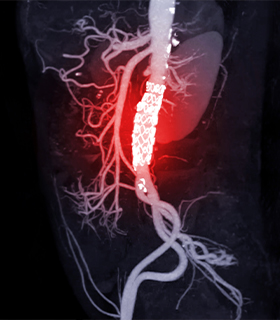

Stroke Surgery

Mechanical thrombectomy and decompressive craniectomies are life-saving surgeries enhancing patient outcomes.